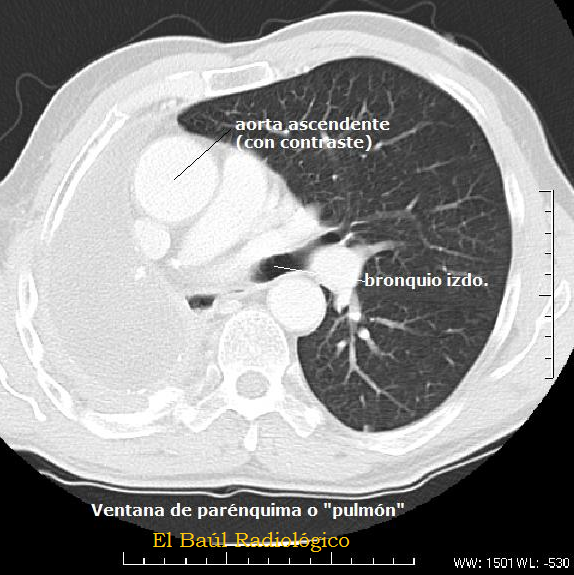

FIGURA 3) Esta imagen se ha obtenido modificando el nivel y la amplitud de ventana, hasta valores apropiados (WW 1500 WL-530)  para examinar el parénquima pulmonar.

(This image was obtained by modifying the level and window width, to values ​​appropriate (WW 1500  WL -530) to examine the lung parenchyma).